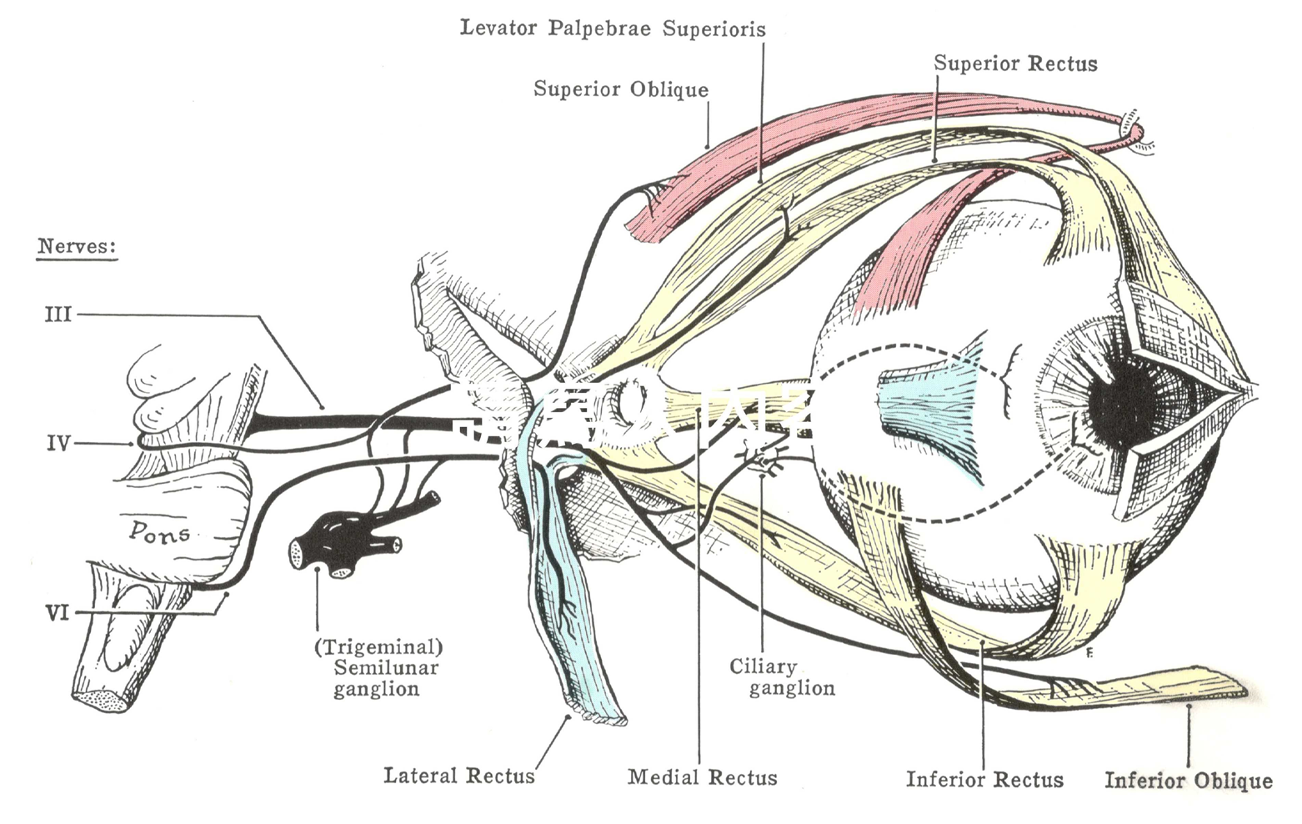

CN III, IV, VI

CN III

- Superior br.

- Motor

- sup. rectus m.

- levator palpebrae superioris m.

- sup. tarsal m.

- Inferior br.

- Motor

- inf. rectus m.

- med. rectus m.

- inf. oblique m.

- Parasympathetic

- ciliary ganglion

- sphincter pupillae m.(瞳孔括約肌)

- ciliary m.(水晶體曲度)

injure

CN IV

Motor

- Sup. oblique m.

injure

複視

CN VI

- Lateral rectus m.